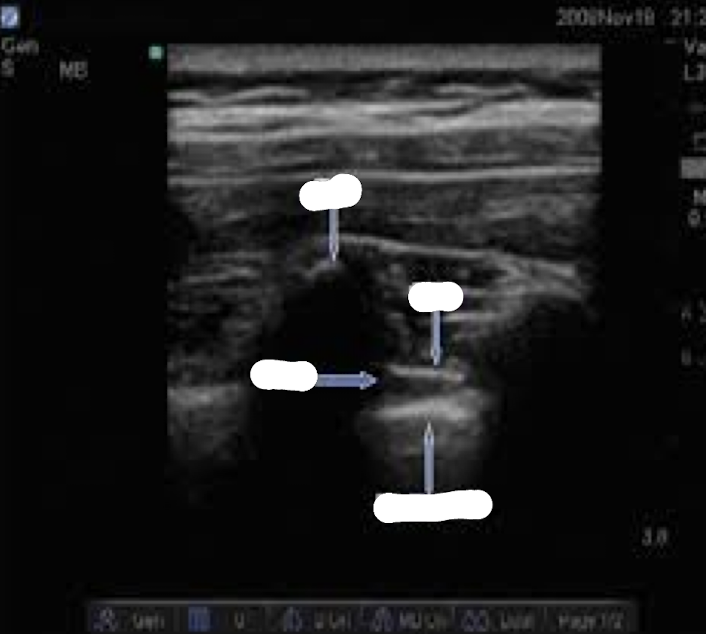

Q

name this block

A

transverse in plane PVB